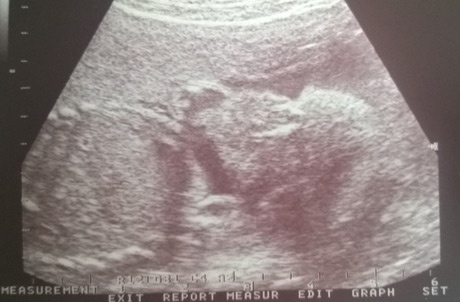

Most már a 27. hétben vagyunk, még a múlthéten meglátogattam az orvosomat. Megnéztük a picilányt, akkor kb. 80 dekára mérte. Olyan kis picurka, de teljesen a korának megfelelő méretekkel rendelkezik. Merthogy én közben orr-fül-gégésztől szájsebészig, fogorvosig rohangáltam az elmúlt hetekben, ugyanis van egy gócpont valahol az arcomban,amit nem találnak. De szülésig elhalasztunk most már minden kezelést. Szigorúan csak orrot lehet fújnom. Azt hiszem már csak ezért is jó lenne szeptemberre ugrani... Még mindig nem lehet?